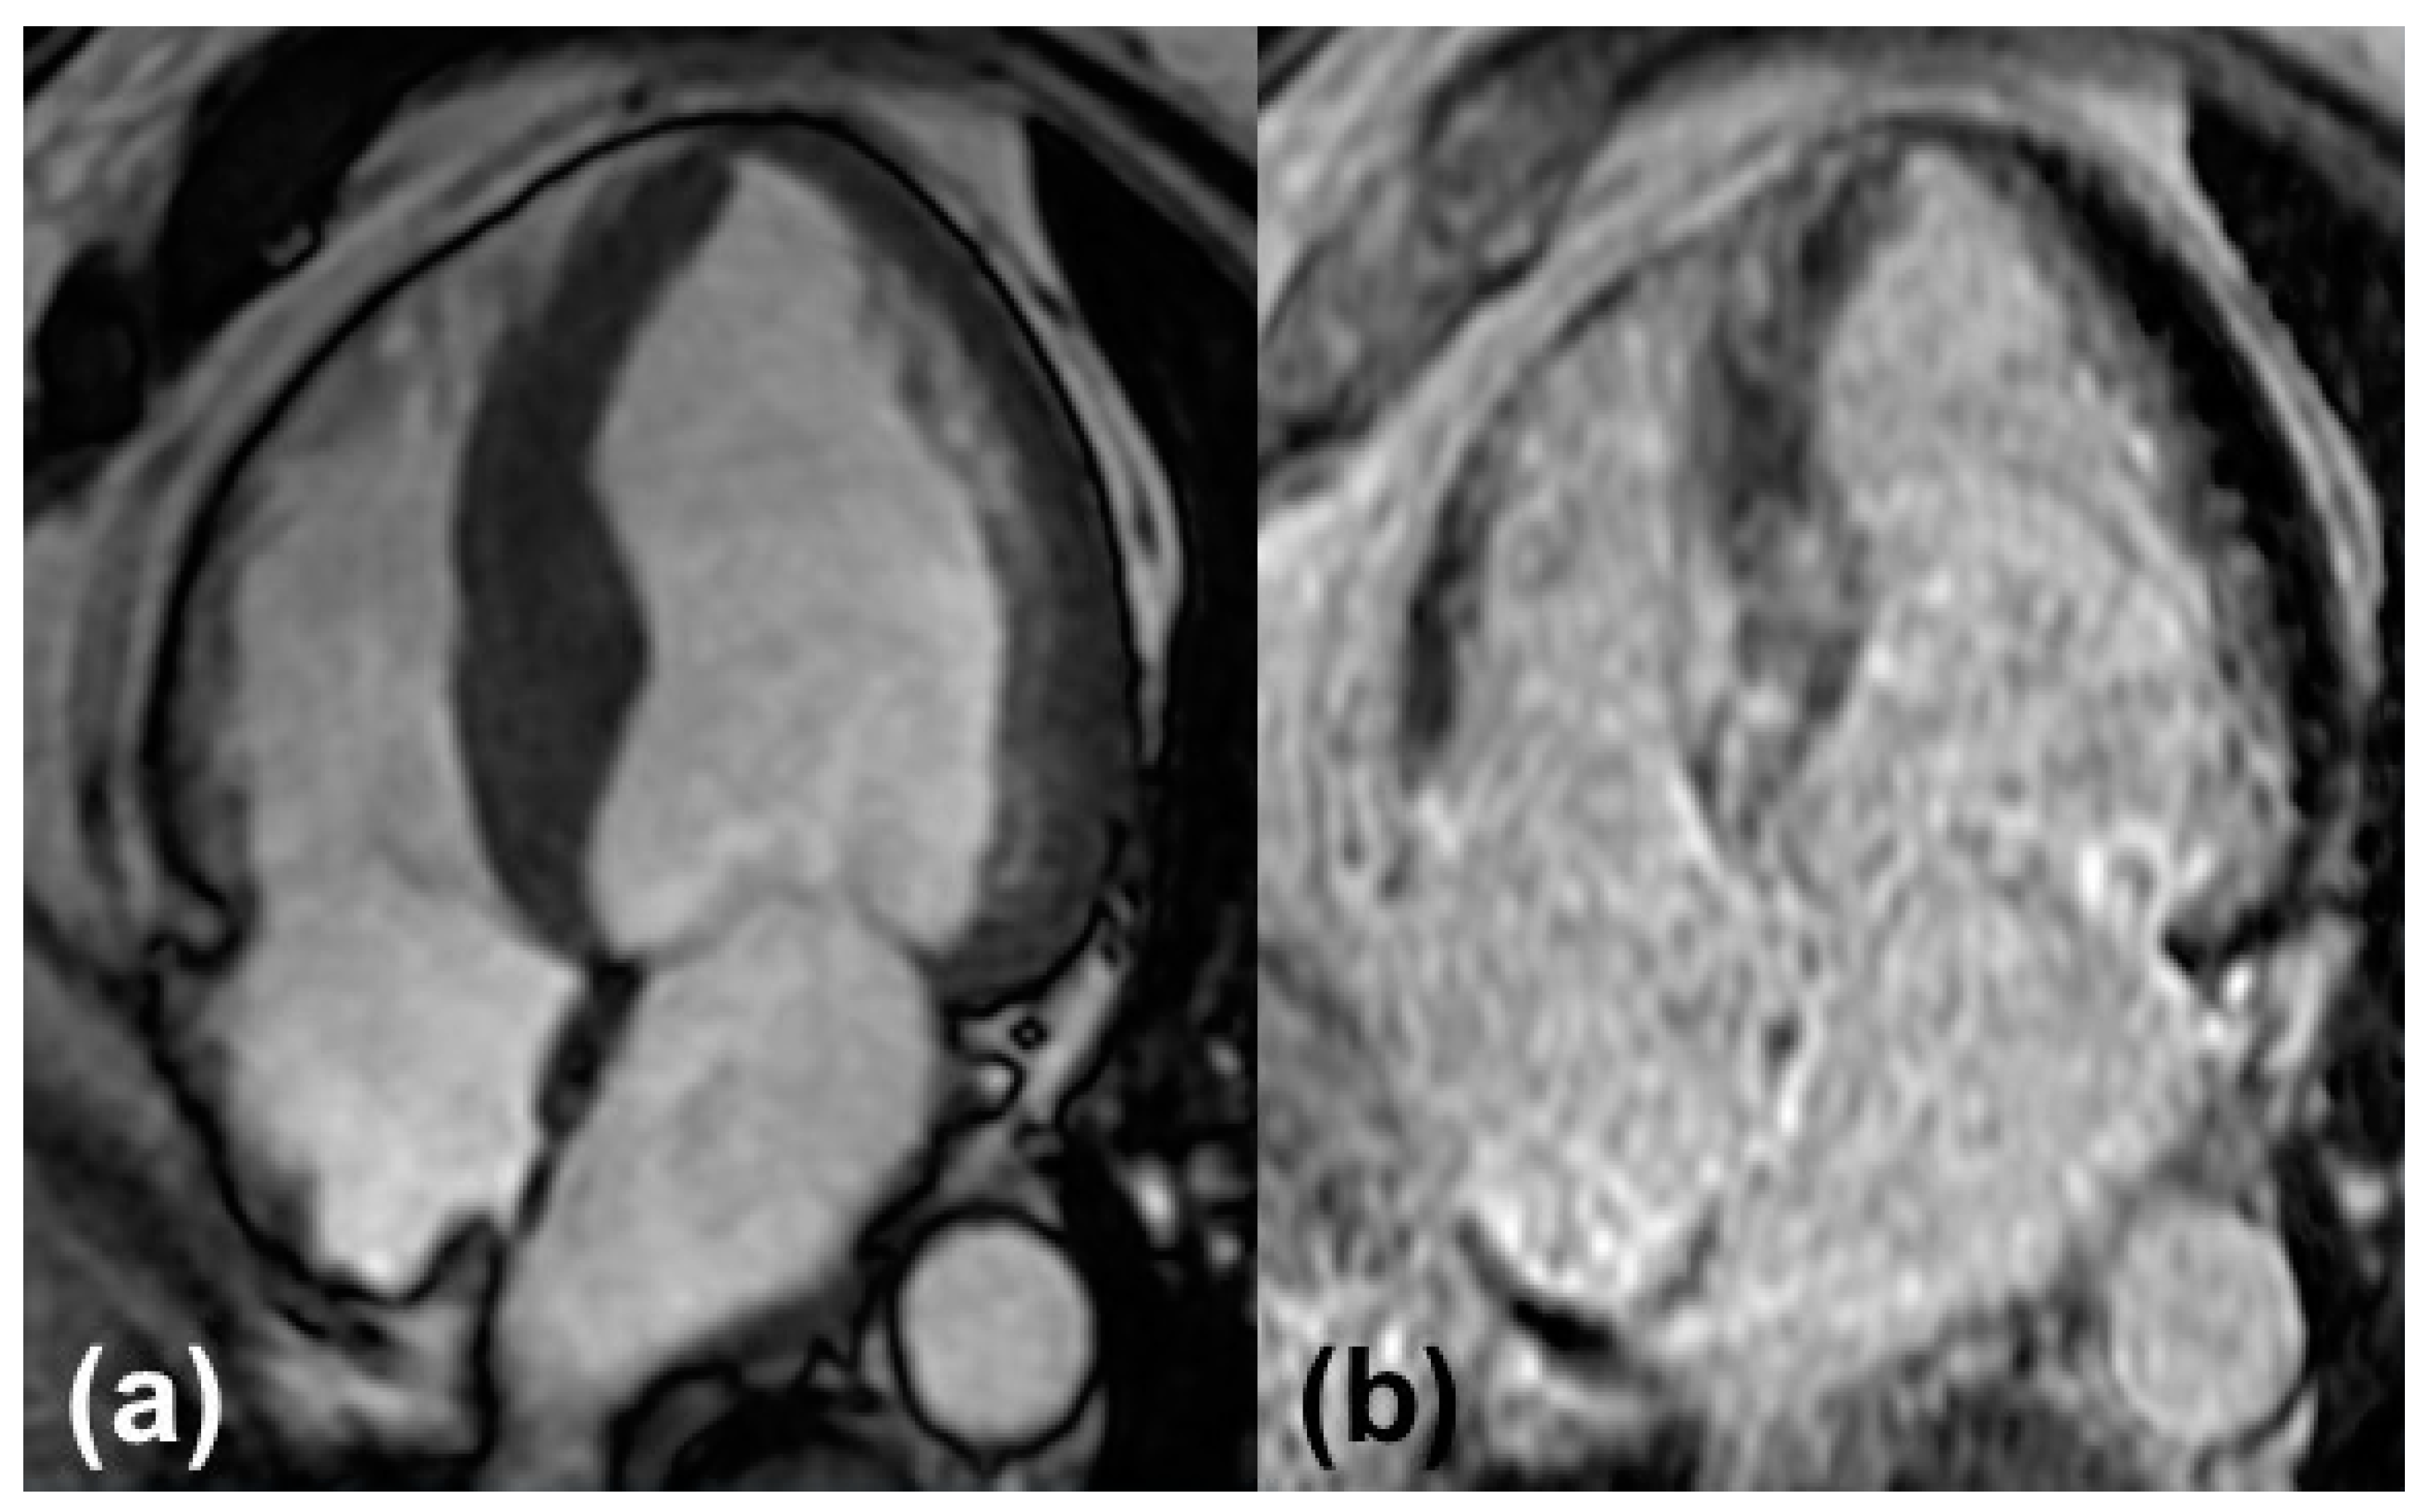

Standardized protocols for image acquisition are strongly recommended by the Society of Cardiovascular Magnetic Resonance (SCMR) [13]. They normally include cine images, native and post-contrast T1 mapping, T2 mapping, and the administration of a gadolinium contrast agent using steady-state free precession sequences (SSFP) (Figure 2). Indications for CA arise from the abnormalities in the standard measurements described in detail below.

Myocardial uptake of gadolinium is referred to as late gadolinium enhancement (LGE). The accumulation of amyloid fibrils leads to the expansion of extracellular space, where gadolinium uptake experiences regional differences depending on the extent of expansion. Patterns range from typically described subendocardial to diffuse, transmural, or patchy dispersion. Though discrimination between different types of CA is not reliably feasible, a study including almost one hundred patients with cardiac involvement of amyloidosis demonstrated that LGE is more extensive in patients with ATTR and there is a higher proportion of patients showing transmural patterns of LGE [14]. Transmural LGE patterns are suggestive for advanced stages of the disease [28]. To our knowledge, there is no established staging system involving LGE.

Figure 2. Typical findings in cardiovascular magnetic resonance: (a) Cine image of a four-chamber view with left ventricular hypertrophy. (b) Late gadolinium enhancement of the left and right ventricular myocardium.